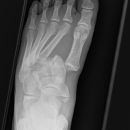

Metatarsale 5

Lisfranc Luxationsfraktur